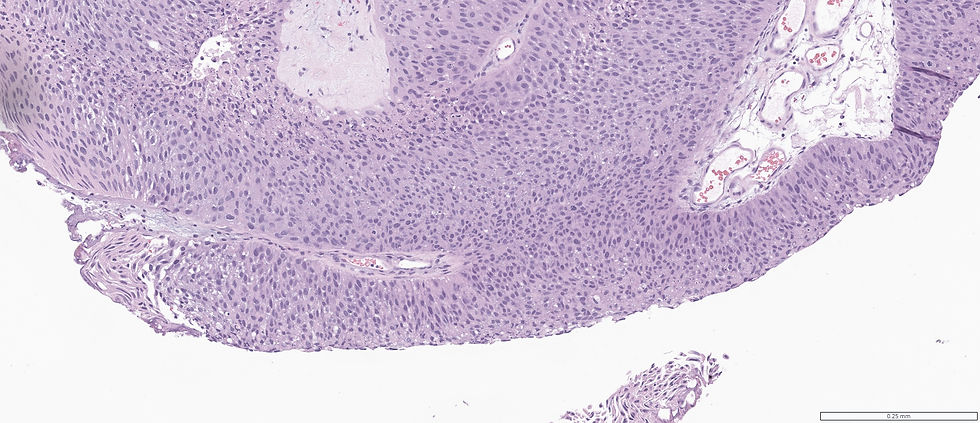

Case 1:

What's your diagnosis?

A. Carcinoma in situ

B. Dysplasia

C: Low grade papillary carcinoma, non-invasive

D: High grade papillary carcinoma, non-invasive

E: Invasive papillary carcinoma

Case 1: High grade papillary carcinoma, non-invasive; Case 2: High grade papillary carcinoma, non-invasive; Case 3: Invasive papillary carcinoma.